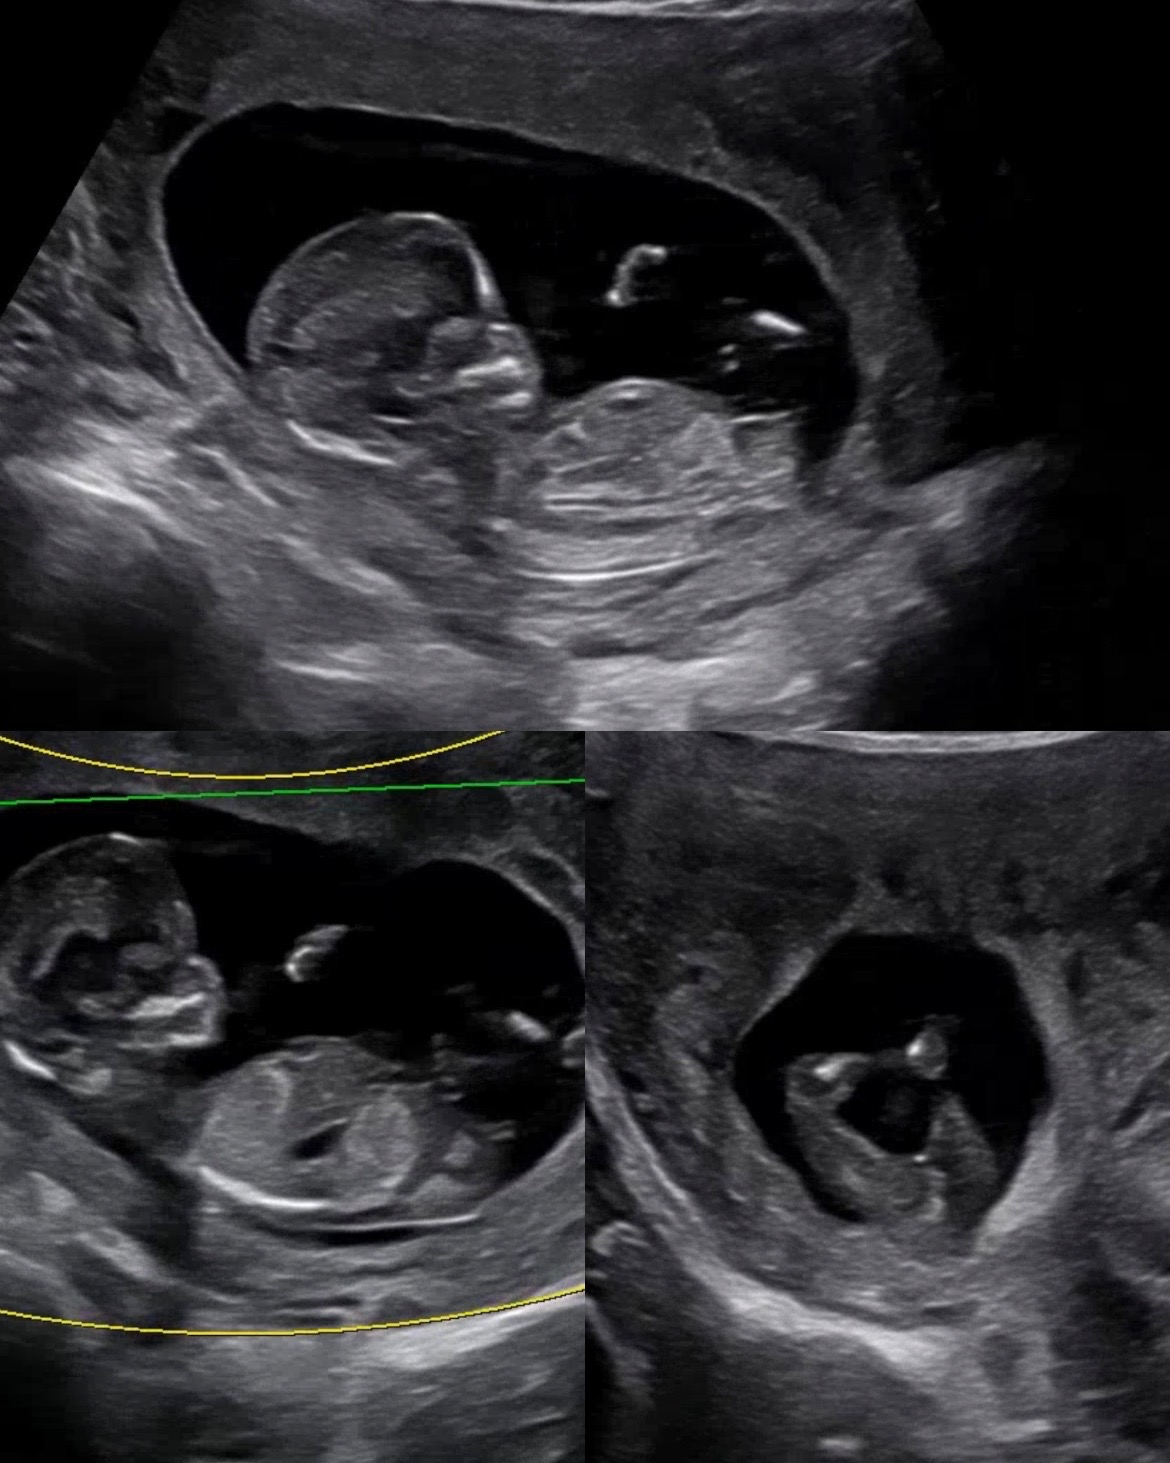

12주4일 각도법 고수님들 봐주세요💛

12주 4일차때 사진인데 어때보이시나요?? 영상의학과, 장꾸맘에서 딸일 가능성이 높다고 했어요!